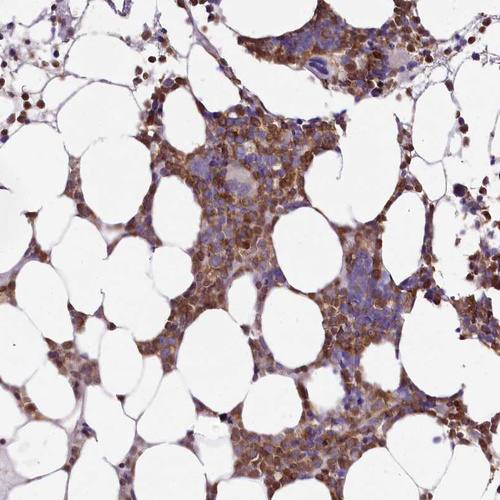

Immunohistochemistry analysis in human tonsil and skeletal muscle tissues using HPA036469 antibody. Corresponding DOCK2 RNA-seq data are presented for the same tissues.